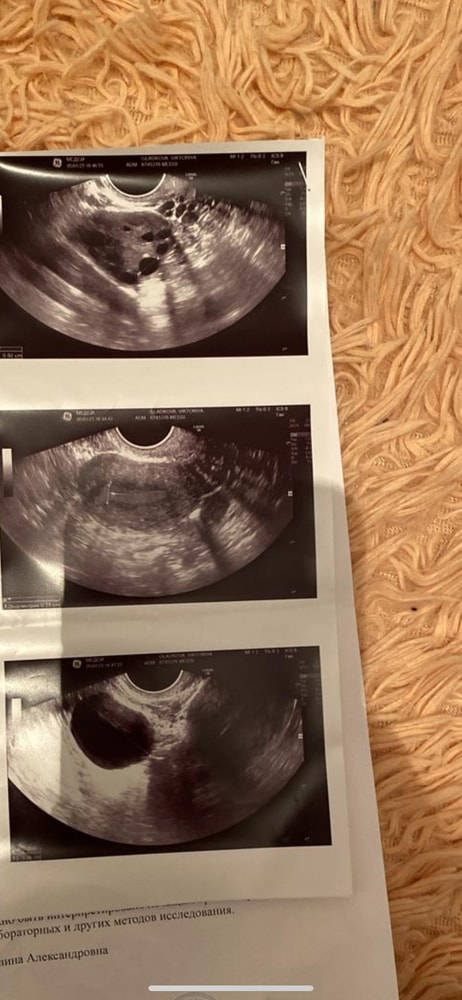

Виктория 5 месяцев Спкя или мфя (узи) Врачи сказали что между спкя и мфя. Посмотрите еще 20 записей на эту тему Лучший ответ Евгения Спкя только по одному узи не ставят, по внешним признакам ( акне , гирсутизм и другие прелести) , цикл, гормоны и тд 21.07.2025 Ответить Отменить Ответить УЗИ Чаты Беременных Выберите чат: Январята-2026 Февралята-2026 Мартята-2026 Апрелята-2026 Майчата-2026 Июнята-2026 Июлята-2026 Августята-2026